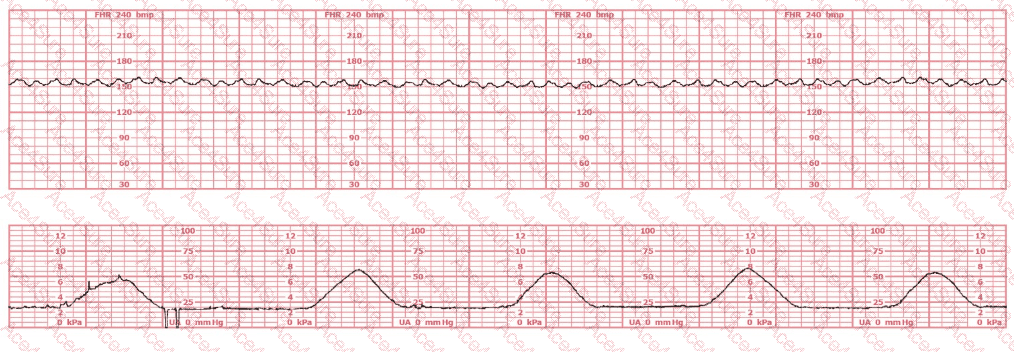

In the tracing provided:

The baseline FHR is approximately 135–145 bpm, within normal limits.

Moderate variability is not consistently present; variability is borderline minimal–moderate at times.

No significant accelerations are seen over the 25-minute evaluation period.

No recurrent late or prolonged decelerations are present.

There are occasional subtle variable-type dips, but not enough to meet criteria for Category III.

NCC-endorsed texts (such as AWHONN and Menihan) state that a tracing with minimal variability for less than 40 minutes and without recurrent decelerations is Category II, as it fails to meet the requirements for Category I (must have moderate variability and accelerations absent decelerations) and lacks the criteria for Category III (must have absent variability with recurrent late decels, recurrent variable decels, bradycardia, or sinusoidal pattern).

Therefore, this pattern is indeterminate, consistent with Category II, and requires continued surveillance and evaluation, which aligns with NCC-recommended clinical decision-making competencies.